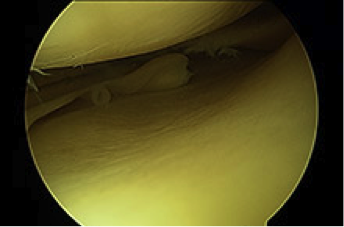

Actualmente la meniscectomía parcial por artroscopia es la intervención más habitual para tratar las roturas del menisco. Consiste en quitar la parte rota e intentar ahorrar el máximo menisco posible, siempre dejando un borde regularizado y estable.

En algunas roturas recientes, en gente joven y que afectan a la parte periférica del menisco, se puede suturar para evitar una extirpación prácticamente total del mismo.